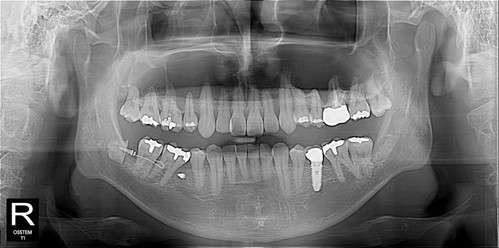

사랑니 발치시 신경손상 위험성으로 치과 교정용 스크류를 이용하여 교정치료와 함께 안전하게 사랑니를 발치한 케이스입니다.

교정력으로 사랑니 뿌리가 신경관과 멀어지기 시작

발치 후 오른쪽도 같은 방법으로 뽑고 싶다고...